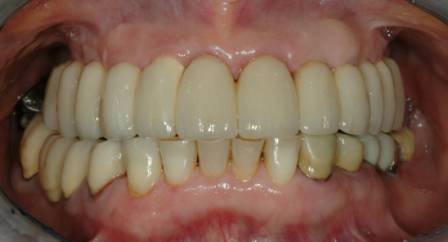

Riabilitazione superiore Implantoprotesi